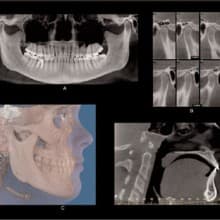

IN THE PAST, DENTAL DAYDREAMERS PONDERED THE ABILITY TO CAPTURE A 3-D IMAGE OF THE MOUTH AND TO VIEW IT FROM ALL ANGLES. The ability to rotate that 3-D mode and zoom in on details was an even greater aspiration. Then, to coordinate all of the information for integration with other applications- such as guided implant placement software-promised to add even more value to the technology. All of these benefits are not just relegated to the dental visionaries of the future. 3-D imaging is available, here and now, and is actively improving practices across all dental disciplines. IMPLANTOLOGY Jack T. Krauser, DMD: 3-D radiography has made an astonishing and

Cone Beam CT: A Breakthrough Imaging Technology for Dentistry

ABSTRACT: Accurate images of the craniofacial region are critical for the development of a diagnosis and treatment plan. The Cone Beam CT (CBCT) Scanner represents a significant advance in imaging capabilities for all disciplines of dentistry. This new-generation scanner uses computed tomography technology to provide a complete three-dimensional view of the maxilla, mandible, teeth, and supporting structures with relatively high resolution and low radiation exposure to the patient. This article discusses some of the technical aspects of CBCT and its possible dental usages. INTRODUCTION: Images of the craniofacial region comprise an important component of the dental patient record. Ideally, the imaging process begins with the development of an imaging goal. The imaging

2-D imaging (standard film and digital X-rays) has long been the standard for dental scans-despite the somewhat costly price and high radiation dosages. Now 3-D imaging technology is set to address these issues. Cone Beam technology obtains crucial information at much higher resolution using lower radiation, and is cost-effective for practitioners and patients. Indeed, such important benefits will certainly give traditional 2-D X-ray imaging a run for its money. THE INTRODUCTION OF CONE BEAM TECHNOLOGY Here's where 3-D imaging is invaluable. It lets dentists see patients' anatomies in all dimensions by creating a 360° analysis. These images give dental professionals a complete makeup of the human jaw, face, and